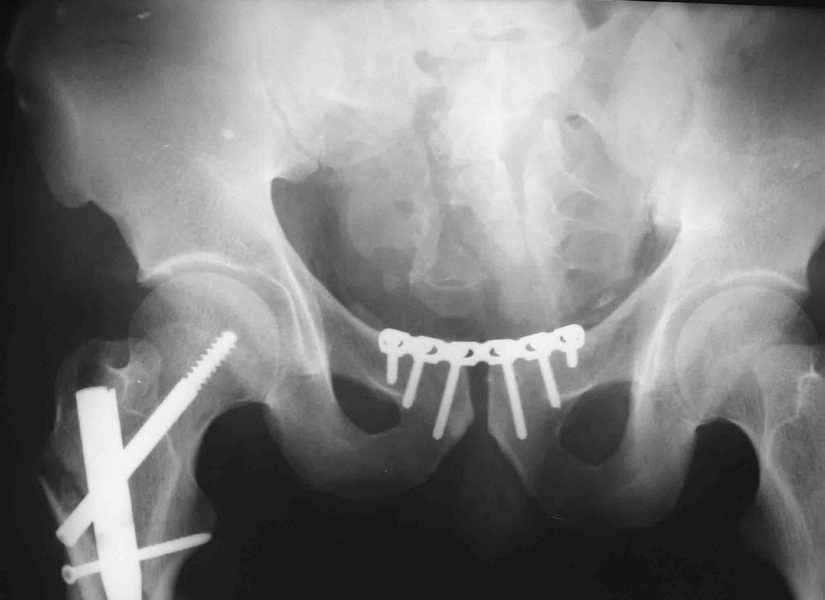

Вот вариант решения похожей ситуации